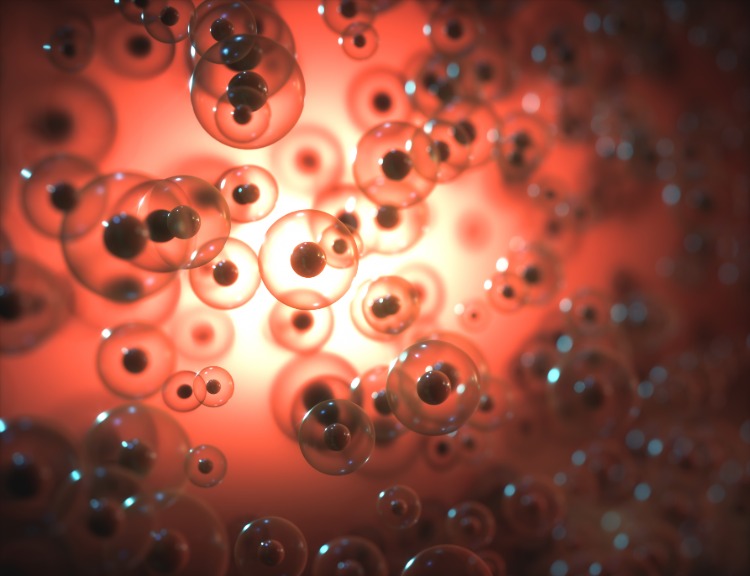

Imunitný systém chráni každú živú bytosť pred útokmi vírusov a baktérií a tiež pomáha likvidovať rakovinové bunky. Vrodená imunita je zodpovedná za počiatočnú detekciu a zničenie invazívnych patogénov. Potom upozorní bunky adaptívneho imunitného systému, ktorý zlikviduje infekčné organizmy a poskytne im dlhodobú ochranu. Existujú však situácie, v ktorých môže byť bunková imunitná odpoveď nesprávne zameraná. Keď sa to stane, imunitný systém zameriava svoju palebnú silu na nesprávne ciele. To sa môže stať buď vlastným proteínom tela v prípade autoimunitných chorôb, alebo cudzím proteínom, ktoré sú samy osebe neškodné, v prípade alergie. Nedávno výskumný tím vedený imunofarmakologičkou Susannou Zierlerovou a farmakologičkou Ingrid Boekhoffovou z Inštitútu pre farmakológiu a toxikológiu Walthera Strauba ukázal, že aktivita určitých proteínov iónového kanála v žírnych bunkách hrá dôležitú úlohu pri prevencii alergických a anafylaktických reakcií. To zaisťuje, že bunková imunitná odpoveď nie je potlačená.

Žírne bunky sa nachádzajú prakticky vo všetkých orgánoch v tele. Regulujú začatie a vyriešenie zápalových reakcií imunitného systému na boj proti infekciám a metabolickým poruchám. Imunitné reakcie sú veľmi zložité procesy, s ktorými je potrebné zaobchádzať opatrne. To znamená, že imunitné bunky musia byť schopné rozpoznať špecifické signály, ktoré interagujú s receptorovými proteínmi na povrchu bunky. Tieto reakcie zahŕňajú zmeny hladín kladne nabitých iónov vrátane vápnika, sodíka a draslíka. Ukazuje sa, že rýchle a prechodné zmeny koncentrácií iónov sú nevyhnutné pre aktiváciu mnohých typov imunitných buniek. Je zrejmé, že bunky regulujú intracelulárne hladiny týchto iónov predovšetkým prostredníctvom bielkovín. Vedci ich označujú ako iónové kanály a iónové pumpy.

Výskumné skupiny teraz charakterizovali funkcie iónových kanálov, ktoré selektívne regulujú koncentráciu voľného vápnika v žírnych bunkách. Tiež skúmali, koľko ďalších bunkových typov žírnych buniek to dosahuje aktiváciou uvoľňovania vápnika z intracelulárnych zásob. Endoplazmatické retikulum (ER) je najväčšou zásobárňou organel pre vápnik v bunkách. V prípade potreby však môžu vápnikové ióny dodávať aj iné intracelulárne organely, ako sú mitochondrie (bunkové elektrárne) a lyzozómy (jednotky na odstraňovanie intracelulárneho odpadu). Všetky tieto intracelulárne kompartmenty sú ohraničené membránami, do ktorých sú vložené špecializované iónové kanály. Zierler, Boekhoff a ich kolegovia uvádzajú, že jeden z nich, TPC1, hrá dôležitú úlohu pri regulácii zmien v intracelulárnej distribúcii iónov vápnika medzi endolysozómami a ER.